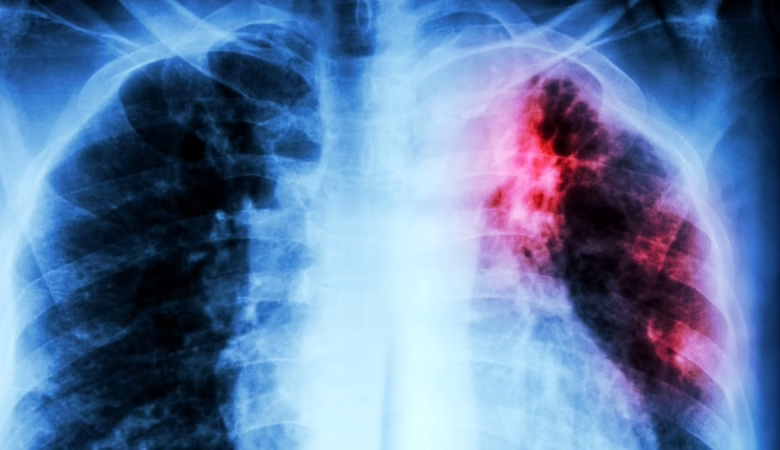

اكتشاف مفتاح جديد لعلاج السُل

كشفت دراسة حديثة أُجريت بجامعة “سيدني” الأسترالية، عن آلية حيوية دقيقة داخل بكتيريا Mycobacterium tuberculosis، المسببة لمرض السل، قد تمثل هدفًا علاجيًا جديدًا، حيث ركّز الباحثون على نظام داخلي مسؤول عن تنظيم جودة البروتينات والحفاظ على توازنها داخل الخلية.